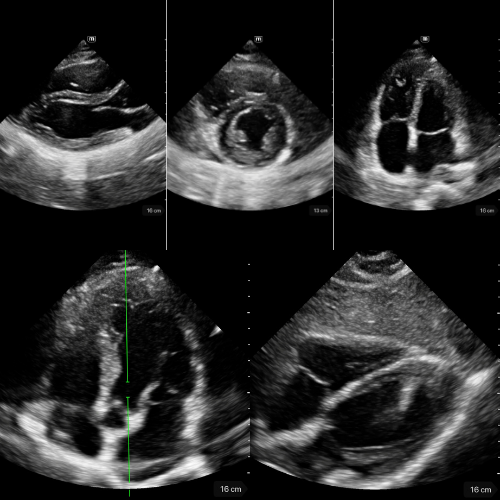

🔹 Vue Parasternale Grand Axe

→ Le cœur se contracte-t-il correctement ?

Sonde au 3ᵉ–4ᵉ espace intercostal gauche, bord sternal, marqueur vers l’épaule droite.

Montre le VG, le VD antérieur, l’oreillette gauche, la valve mitrale, la valve aortique et la racine de l’aorte.

On y évalue :

- la contractilité du VG ;

- la présence d’un épanchement péricardique postérieur ;

- l’aspect de la racine aortique (dilatée, disséquée, hyperéchogène) et la mesure de la chambre de chasse du VG.

🔹 Vue Parasternale Petit Axe

→ La contraction est-elle harmonieuse ?

Même point d’appui que pour le parasternal grand axe, rotation à 90°, marqueur vers l’épaule gauche.

On observe la coupe circulaire du VG et du VD.

Un VG rond, contractile et homogène = fonction normale.

Un VG aplati ou en “D” = surcharge droite (embolie pulmonaire, HTP, tamponnade).

Une zone hypokinetique/akinetique = ischémie segmentaire.

Vue reine pour la fonction systolique et le septum interventriculaire.

Un léger mouvement de bascule permet d’explorer trois niveaux distincts :

- le plan de la valve mitrale

- le plan des muscles papillaires

- le plan de la valve aortique avec son aspect caractéristique en « signe Mercedes ».